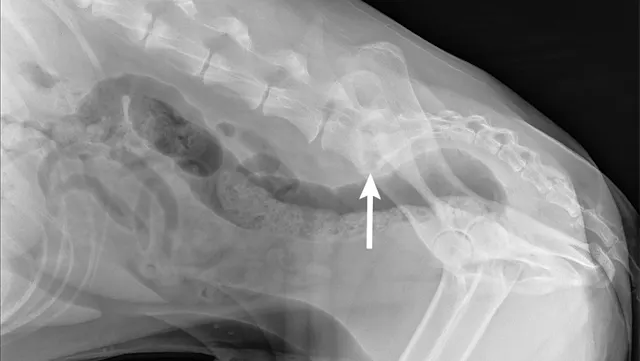

Spinal radiography was performed, and lysis at the L7 and S1 endplates was identified (Figures 4 and 5).